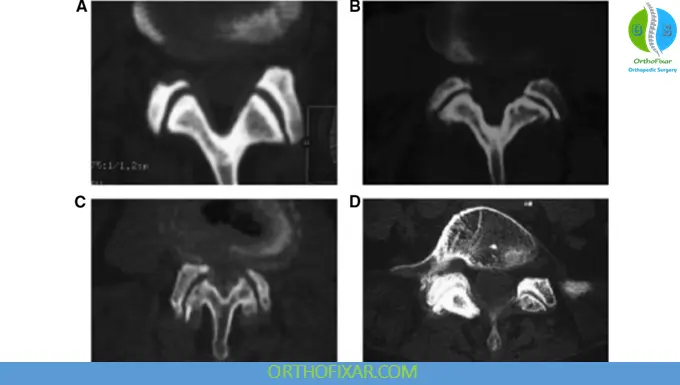

Facet Arthropathy Grading

The Pathria et al. classification system is a widely used 4-grade scale for evaluating facet joint (FJ) arthropathy, or osteoarthritis (OA), primarily using computed tomography (CT) and, in some contexts, plain radiographs:

- Grade I (Normal/Mild): Normal facet joint space (typically 2-4 mm), with no, or minimal, osteophytes and/or mild articular process hypertrophy. Some sources define this as mild, noting joint space narrowing.

- Grade II (Moderate): Mild to moderate joint space narrowing ((<2) mm) with subchondral sclerosis, and/or small osteophytes, and/or mild articular process hypertrophy.

- Grade III (Severe): Further joint space narrowing ((<1) mm or “bone to bone”), with subchondral sclerosis, and/or moderate osteophytes.

- Grade IV (Very Severe): Severe osteoarthritis with complete absence of joint space (arthrodesis or “bone on bone”) and/or large osteophytes.